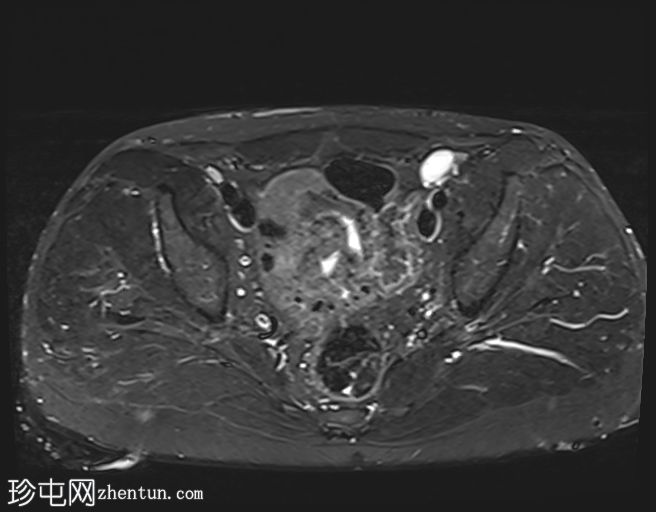

MRI

左侧阴囊空虚。

左侧睾丸位于盆腔左侧前壁,腹股沟管上方。其体积较小(与对侧正常的右侧睾丸相比)。T2加权像呈高信号,T1加权像呈低信号,未见明显局灶

性病

变。

右侧睾丸位于右侧阴囊内,大小和形状正常。

病例讨论

患者已知患有隐睾。评估睾丸大小以判断是否存在萎缩(本例已证实)以及是否存在任何睾丸局灶性病变非常重要。隐睾患者发生恶性

肿瘤

的风险较高。本例未见睾丸肿块。